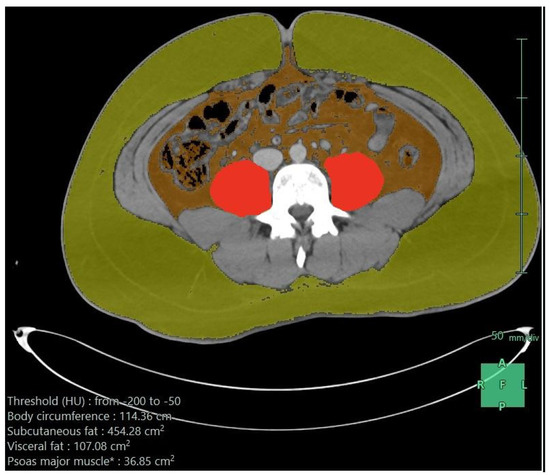

Table 2 shows the first dietary order details on admission and after the first week. On admission, 56% received oral feeding, and this slightly increased to 58.4% after the first week. Enteral feeds were used for the remaining, except for two patients: one needed parenteral nutrition on admission and another needed it after the first week. Nasogastric tubes were the most common enteral access on admission and after the first week. The enteral formula was the standard 1:1 (1 mL provides 1 kilocalorie) in the majority (95%) of cases. On admission, the elemental formula was used in 67%, dropping to 17% after the first week, where the standard formula was more frequent (39%). High-protein formulas were only used after the first week in 20%. On admission, the median infusion rate was low— 20 mL/h versus 70 mL/h after one week—which provided fewer calories initially (median 600 K) and increased after one week (2000 K), and the median protein amounts were 51 g initially, which increased to 113 g after the first week. It was well tolerated, and the nutritional target was sufficient on admission in 40%, which increased to 71% after one week. These findings reflected a clear undernutrition achievement on admission and after the first week. Regardless of the increased needs due to trauma, there were multiple other factors. The associated body responses, complications, and interruption of feeding were related to nil per os (NPO) orders for procedures or feeding intolerance, particularly in those who underwent abdominal surgeries with postoperative ileus or NPO standard orders if bowel resection and anastomosis were used. Figure 1 shows the axial CT image after processing, demonstrating subcutaneous fat, visceral fat, psoas muscle, and para-spinal muscles.

Figure 1.

Axial CT scan image after processing (subcutaneous fat in greenish yellow, visceral fat in brown color, and psoas muscle in red color); the measurements are given in the lower part of the image.